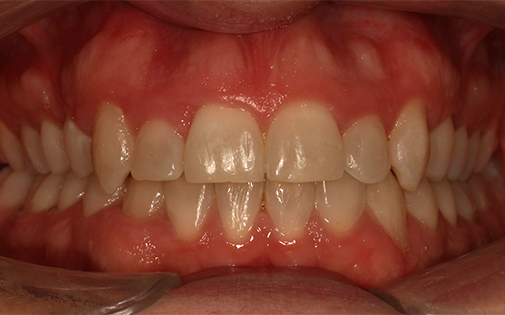

This patient presented with a very severe malocclusion (i.e. irregularity of her teeth and jaws). The ideal treatment recommended was removal of four teeth, upper and lower fixed braces and surgery to her jaws. However, the patient was not keen on the idea of surgery so she offered the alternative of removal of two upper teeth and Invisalign clear aligners. With the expertise of our specialist orthodontists, even the most challenging cases can be treated successfully with Invisalign.